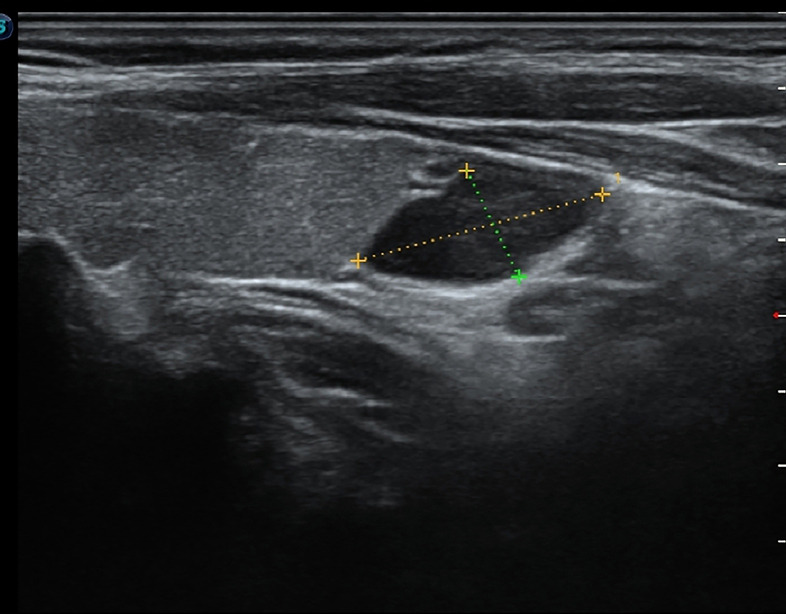

Abstract Image